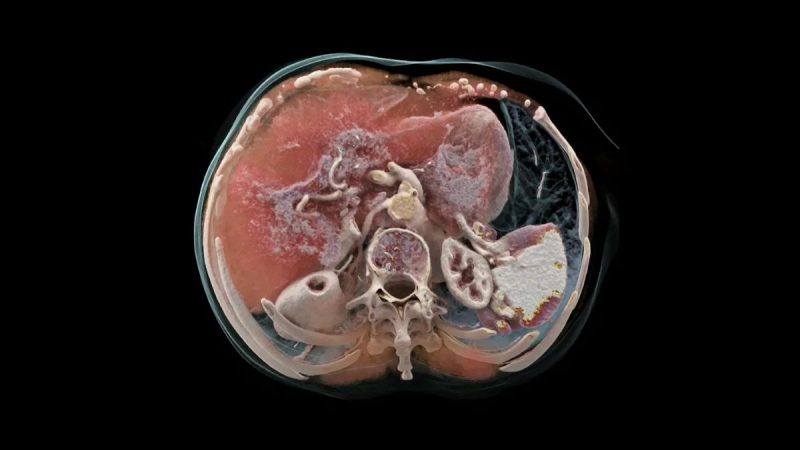

En cuanto a los pacientes, los beneficios de los nuevos modelos de TC de Siemens Healthineers , son también destacables. María de Oyarzabal, nos ha explicado que el aparato al ofrecer una mayor resolución en oncología permite, por ejemplo, «detectar tumores como el mieloma múltiple, ya que gracias a esa mayor calidad en la imagen que ofrece se pueden ver estructuras más pequeñas que otros aparatos».

Estas son algunas de las ventajas para los pacientes, pero para los clínicos también las hay. Algunas ya se han mencionado, aunque en líneas generales es importante destacar que la tecnología avanzada que incorpora este aparato ofrece no solo una información anatómica de la imagen, sino también funcional. «Es decir, muestra detalles de cómo está funcionando el cerebro, el vaso sanguíneo o la parte del cuerpo que se está analizando. Además, es posible apreciar estructuras anatómicas pequeñas como el oído interno, y todo ello redunda al final en un diagnóstico más precoz y una mejora en el tratamiento del paciente».